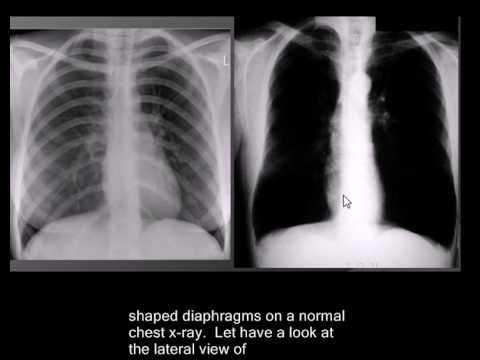

what is the xray results of emphysema?

A

1. flattened diaphgram

2. bilaterally hyperlucent lungs of large volume

3. widened costophrenic angles and horizontal ribs

4. narrow mediastinum